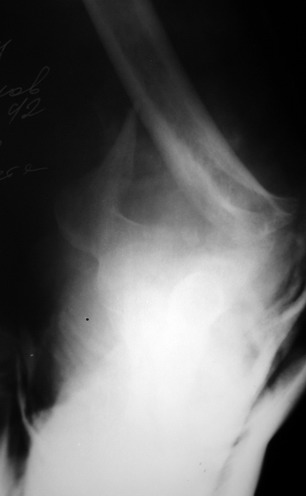

Солидарен с мнением обоих Александров (Челнокова и Рыкова): точную репозицию такого перелома вряд ли удастся выполнить закрыто. Даже во время открытого вмешательства это сделать непросто. Неслучайно предложен костно-пластический доступ с временным отсечением локтевого отростка. И по методу фиксации согласен с Александром Челноковым: 2 пластины. В качестве примера привожу рентгенограммы одного из наших пациентов с аналогичным повреждением.